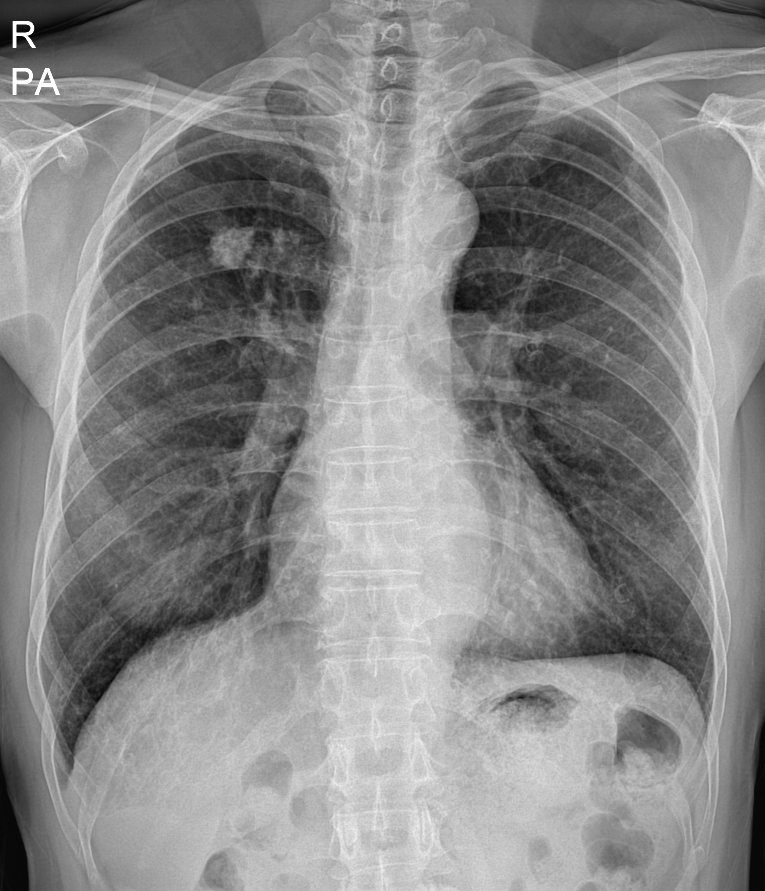

45세 남자

왼쪽부터 폐렴 진단 1년 전 흉부 엑스레이, 진단 당시 우상엽 폐렴